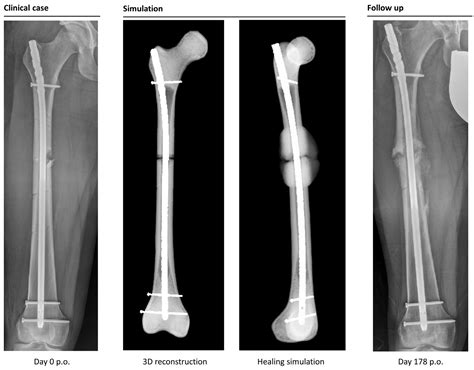

Broken femur types, causes, treatment, recovery time & complications